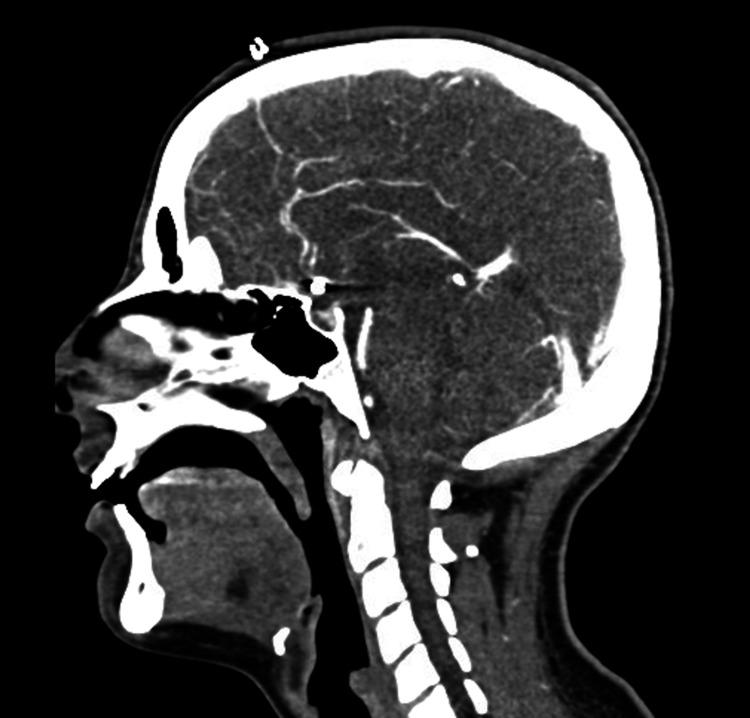

Preeclampsia is a type of hypertensive disorder of pregnancy that can cause significant maternal and perinatal morbidity and mortality. Hypertension and proteinuria are the keystones of the disease, though systemic end-organ dysfunction may follow. The pathogenesis is multifactorial, with known influences by placental, vascular, renal, and immunological dysfunction. This is a case of preeclampsia complicated by preterm delivery and antepartum intracerebral hemorrhage secondary to aneurysm rupture, presenting as dull headaches and blurry vision, commonly associated with severe features.

子痫前期是一种妊娠期高血压疾病,可导致严重的孕产妇和围产期发病及死亡。高血压和蛋白尿是该疾病的关键特征,尽管随后可能出现全身终末器官功能障碍。其发病机制是多因素的,已知受胎盘、血管、肾脏和免疫功能障碍的影响。这是一例子痫前期合并早产和动脉瘤破裂继发产前脑出血的病例,表现为钝痛和视力模糊,通常伴有严重特征。